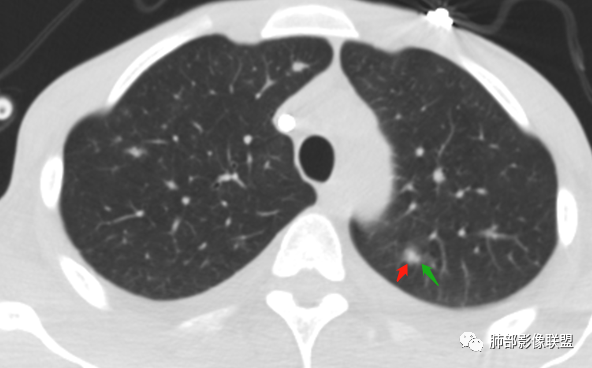

2.双肺散在不规则小片状影及结节影,部分可见磨玻璃晕。结节影边界较清楚。左肺片影边界不清,范围较大,支气管相关,支气管壁增厚不明显,病灶内见液化空洞。

3.肺炎型肺部影像学表现常为双肺多发片影,肉芽肿样结节影,边界相对清楚,可见磨玻璃晕,部分病灶可显示坏死空洞。部分病例出现胸水。支气管炎型病例可见较广泛支气管壁增厚。